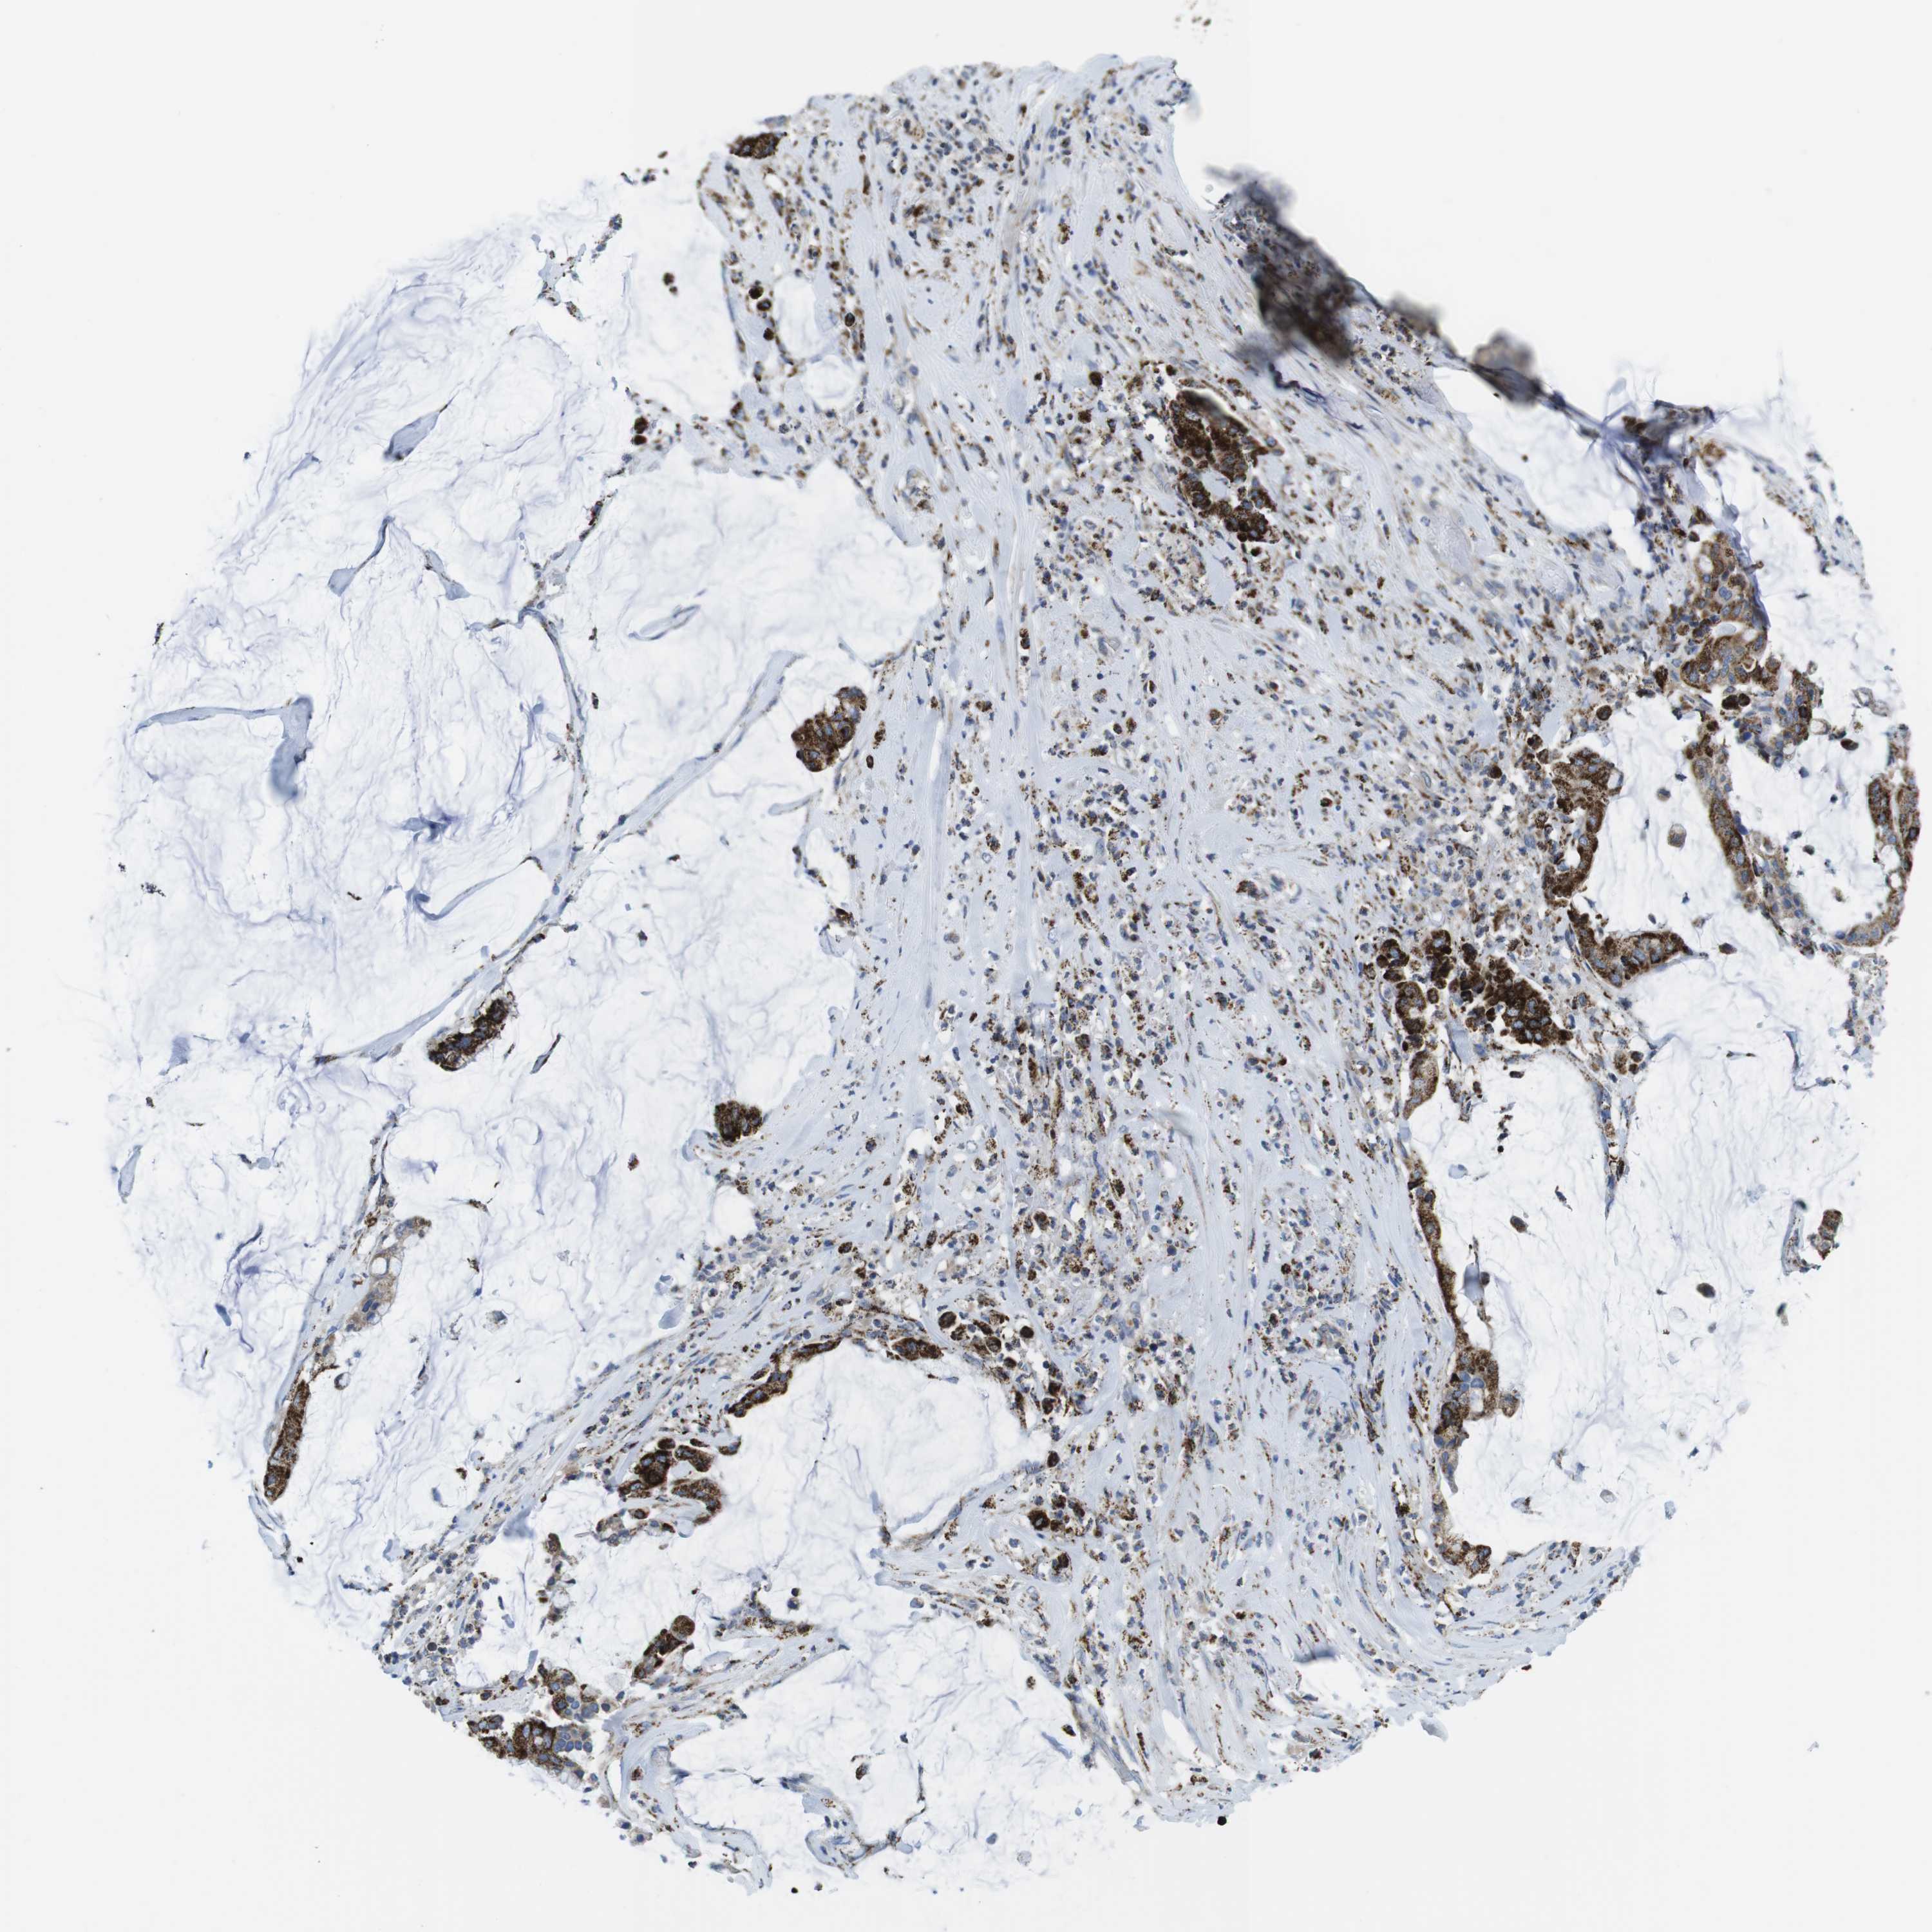

PANCREATIC CANCER - Protein expressioni

A mouse-over function shows sample information and annotation data. Click on an image to view it in a full screen mode. Samples can be filtered based on level of antibody staining by selecting one or several of the following categories: high, medium, low and not detected. The assay and annotation is described here.

Note that samples used for immunohistochemistry by the Human Protein Atlas do not correspond to samples in the TCGA dataset.

Antibody stainingi

Antibody staining in the annotated cell types in the current human tissue is reported as not detected, low, medium, or high, based on conventional immunohistochemistry profiling in selected tissues. This score is based on the combination of the staining intensity and fraction of stained cells.

Each image is clickable and will lead to virtual microscopy that enables deeper exploration of all samples and also displays staining intensity scores, fraction scores and subcellular localization as well as patient and tissue information for each sample.

Antibody HPA014849

Staining

High

Medium

Low

Not detected

Intensity

Strong

Moderate

Weak

Negative

Quantity

>75%

75%-25%

<25%

None

Location

Nuclear

Cytoplasmic/membranous

Cytoplasmic/membranous,nuclear

Adenocarcinoma, NOS